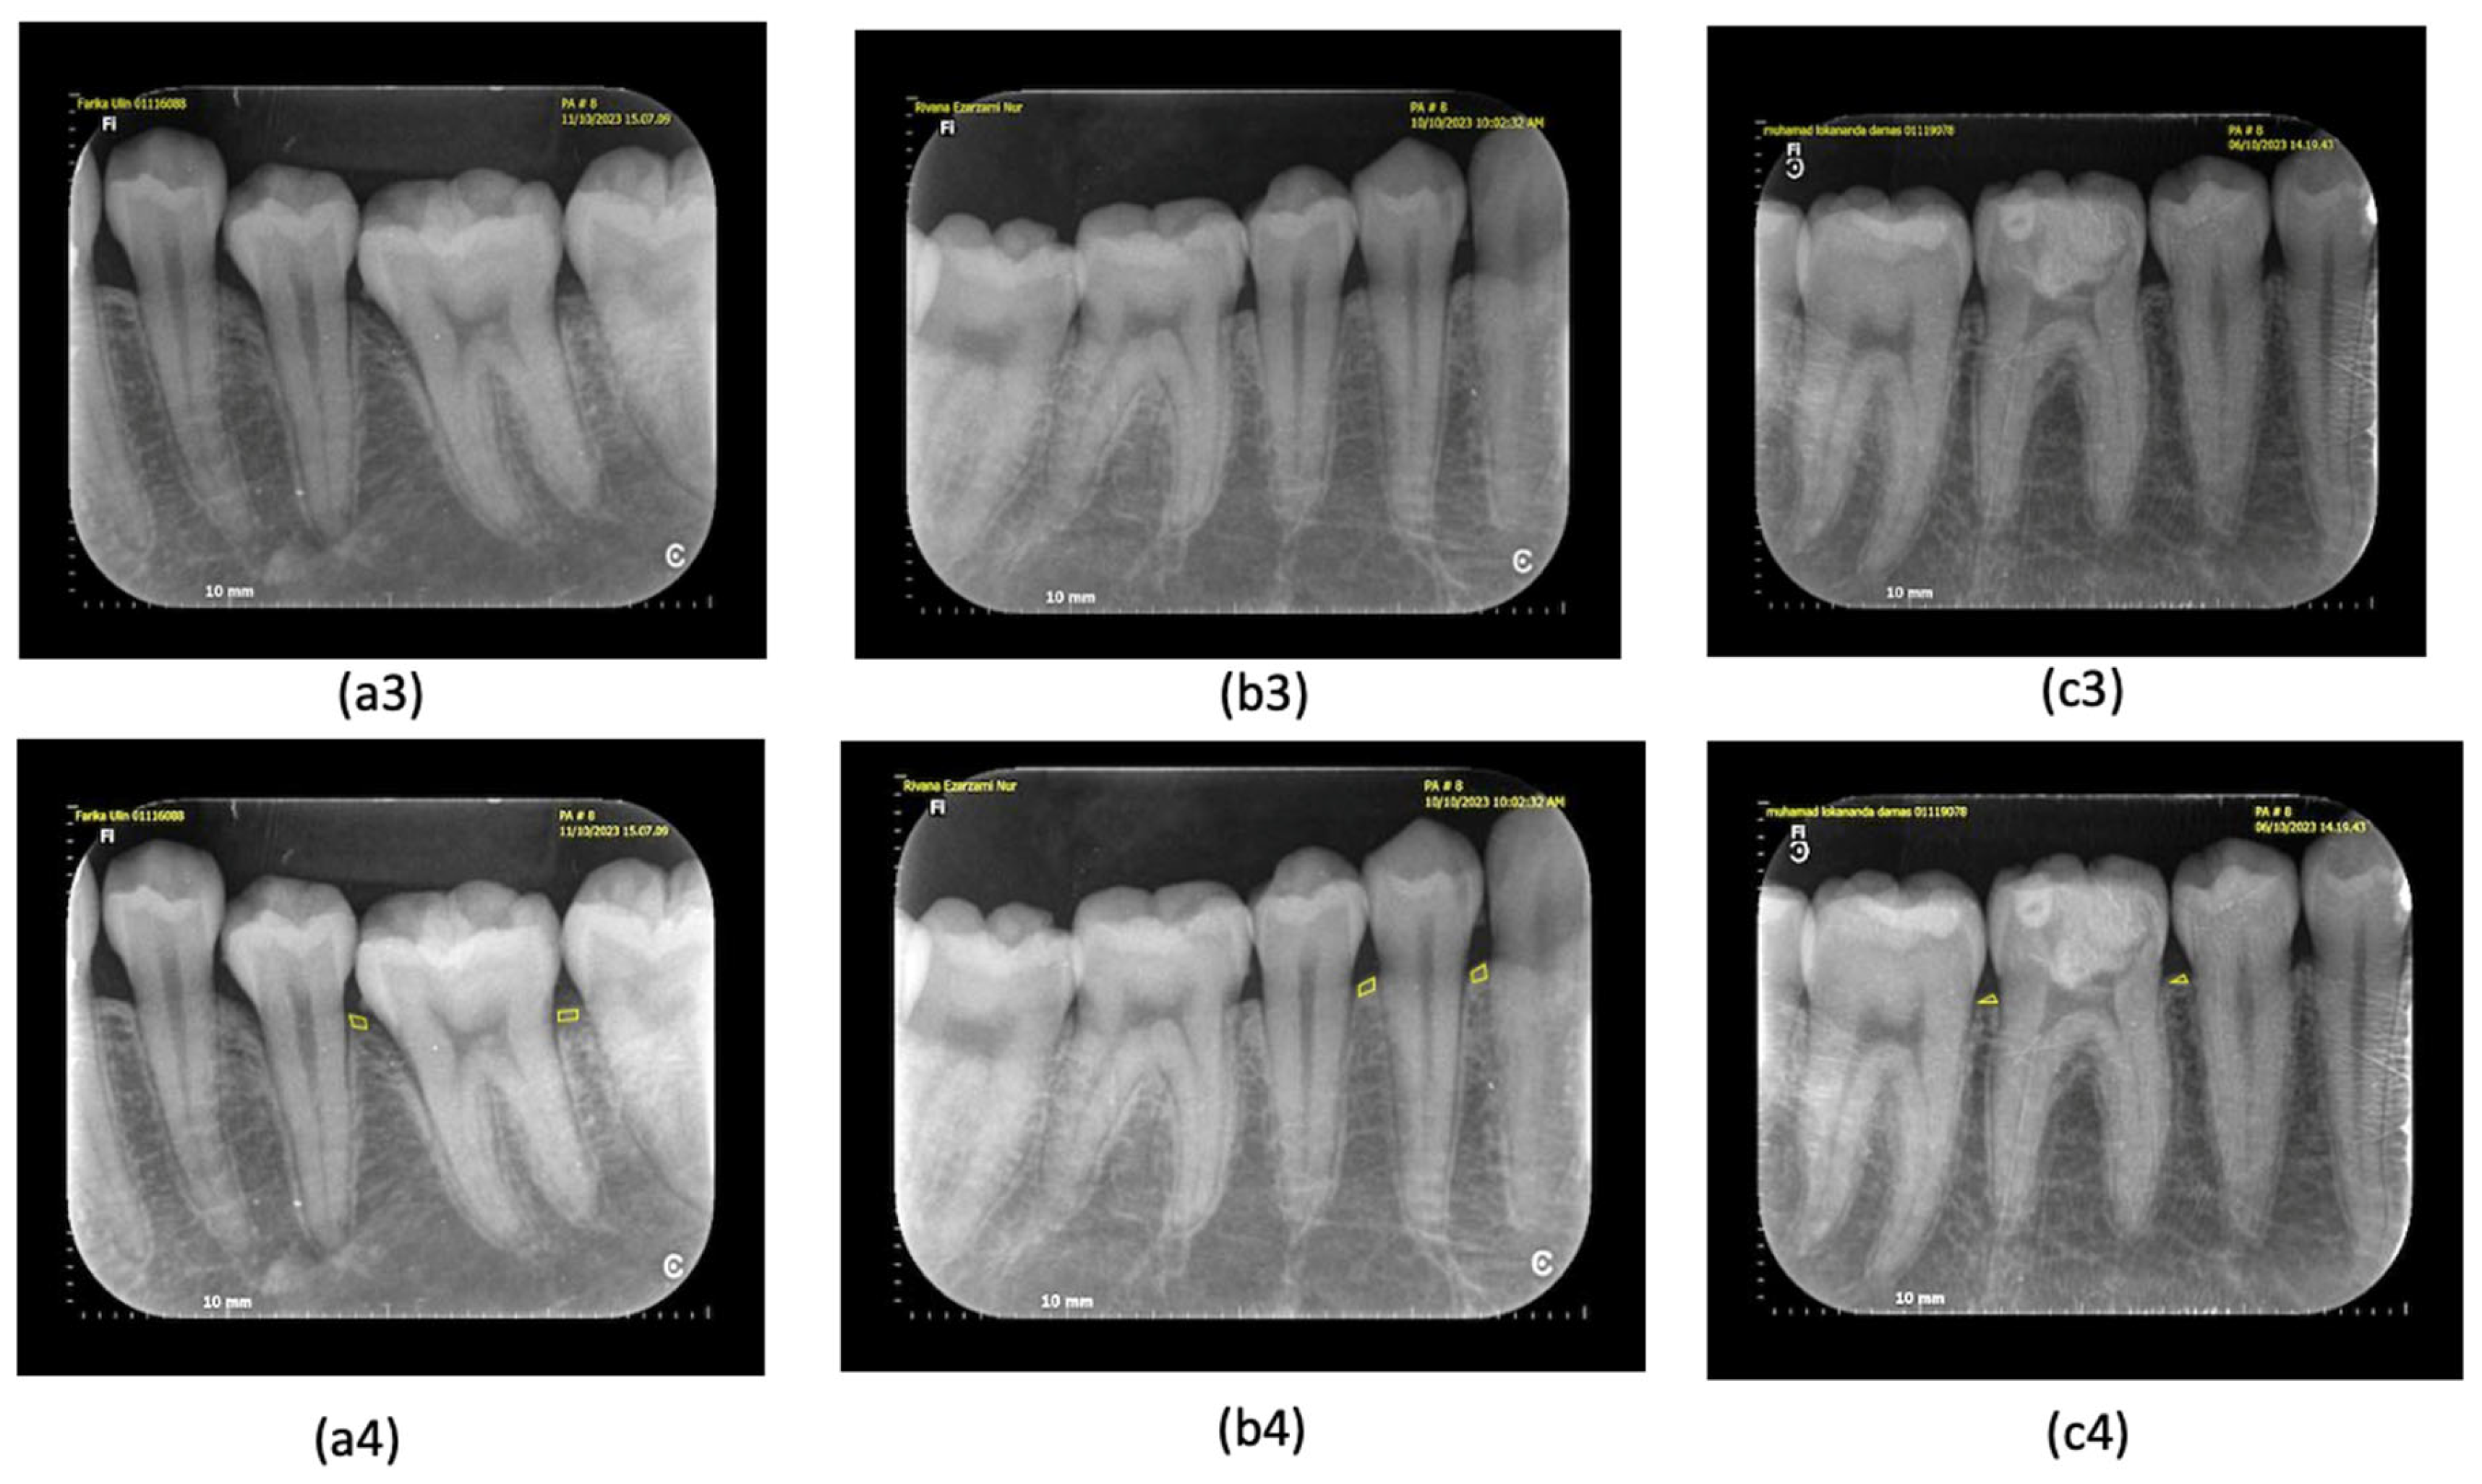

2.2. Set of Clinical Examination and Periapical Radiograph